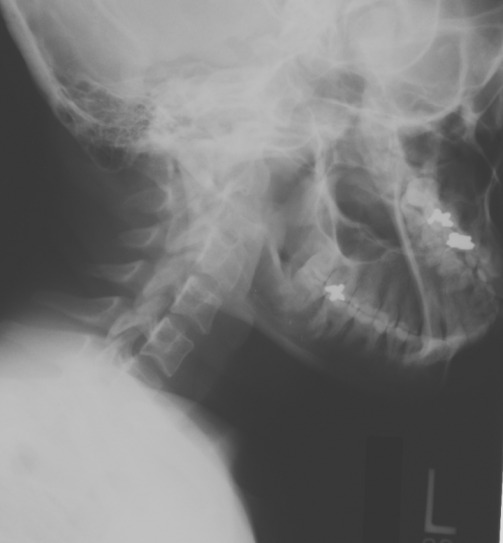

17 year old male post MVA.

1. Describe your findings.

2. What are some of the causes this condition?